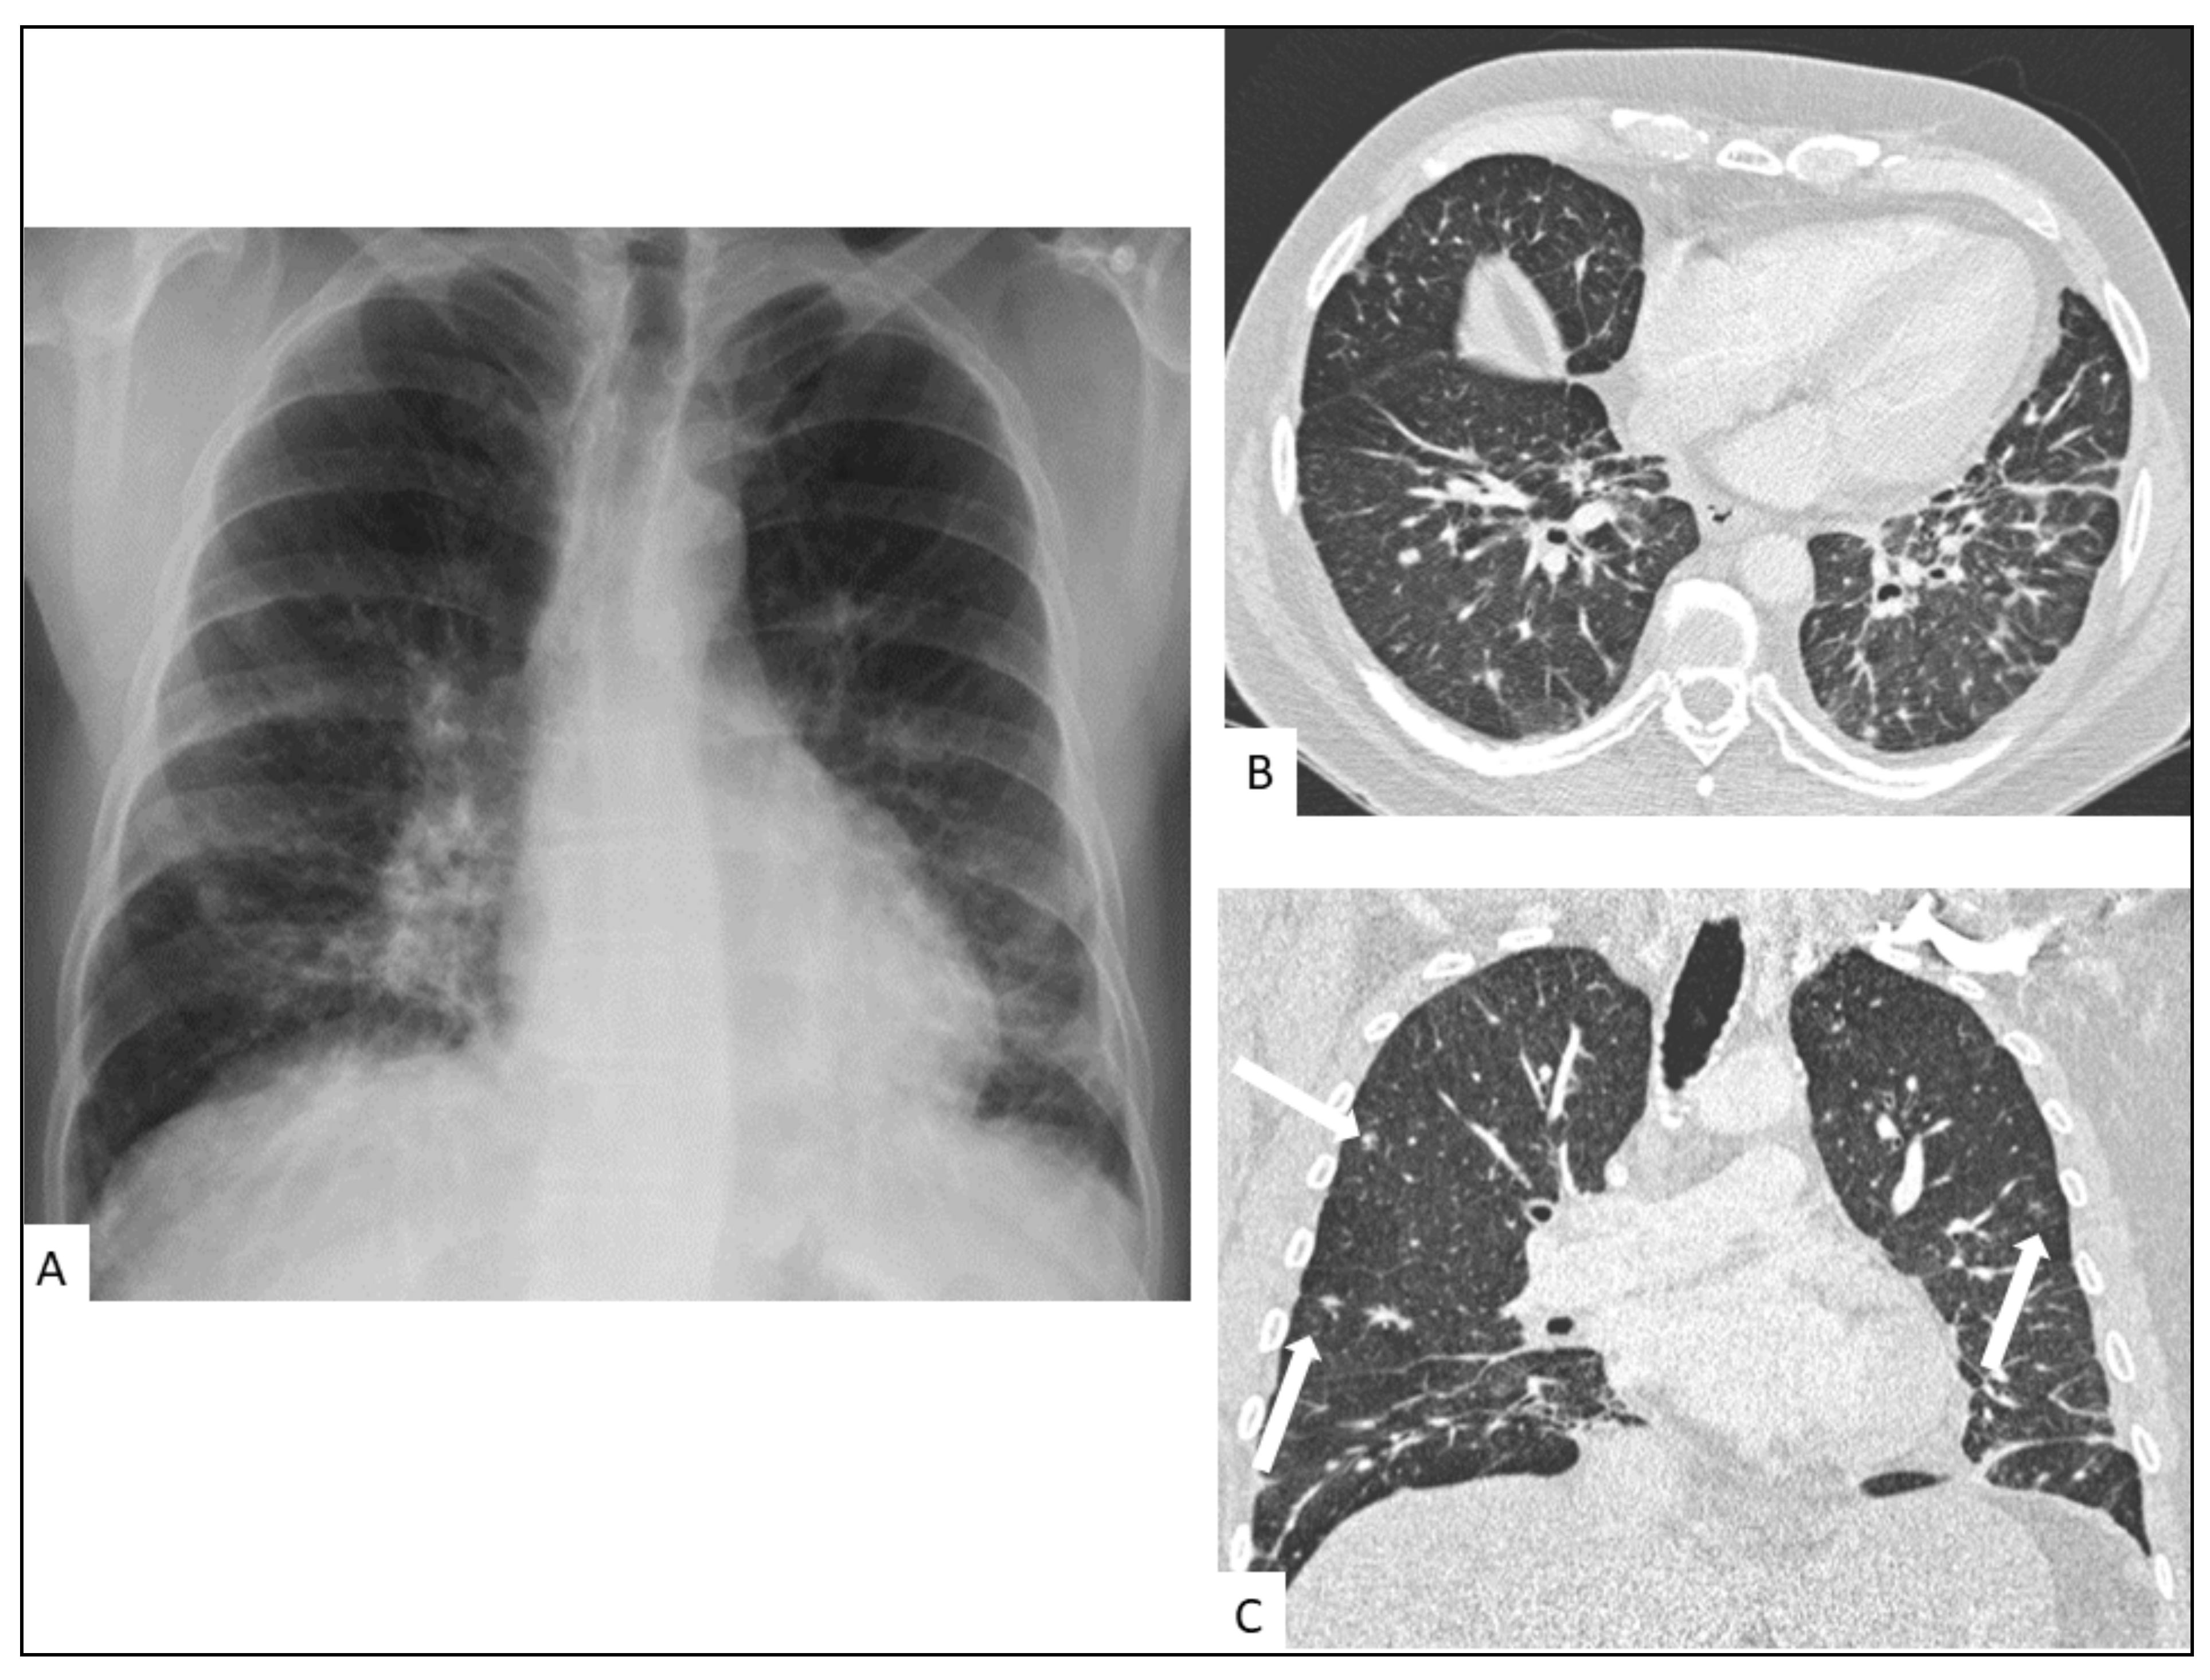

5.1. Pulmonary KS

- Restrepo, C.S.; Martínez, S.; Lemos, J.A.; Carrillo, J.A.; Lemos, D.F.; Ojeda, P.; Koshy, P. Imaging Manifestations of Kaposi Sarcoma. Radiographics 2006, 26, 1169–1185. [Google Scholar] [CrossRef]

- Traill, Z.C.; Miller, R.F.; Shaw, P.J. CT Appearances of Intrathoracic Kaposi’s Sarcoma in Patients with AIDS. Br. J. Radiol. 1996, 69, 1104–1107. [Google Scholar] [CrossRef]

- Khalil, A.M.; Carette, M.F.; Cadranel, J.L.; Mayaud, C.M.; Bigot, J.M. Intrathoracic Kaposi’s Sarcoma. CT Findings. Chest 1995, 108, 1622–1626. [Google Scholar] [CrossRef]

- Gasparetto, T.D.; Marchiori, E.; Lourenço, S.; Zanetti, G.; Vianna, A.D.; Santos, A.A.S.M.D.; Nobre, L.F. Pulmonary Involvement in Kaposi Sarcoma: Correlation between Imaging and Pathology. Orphanet J. Rare Dis. 2009, 4, 18. [Google Scholar] [CrossRef]

- Javadi, S.; Menias, C.O.; Karbasian, N.; Shaaban, A.; Shah, K.; Osman, A.; Jensen, C.T.; Lubner, M.G.; Gaballah, A.H.; Elsayes, K.M. HIV-Related Malignancies and Mimics: Imaging Findings and Management. Radiographics 2018, 38, 2051–2068. [Google Scholar] [CrossRef]

- Da Silva Filho, F.P.; Marchiori, E.; Valiante, P.M.; Escuissato, D.L.; Gasparetto, T.D. AIDS-Related Kaposi Sarcoma of the Lung Presenting with a "Crazy-Paving" Pattern on High-Resolution CT: Imaging and Pathologic Findings. J. Thorac. Imaging 2008, 23, 135–137. [Google Scholar] [CrossRef]

- Allen, C.M.; Al-Jahdali, H.H.; Irion, K.L.; Al Ghanem, S.; Gouda, A.; Khan, A.N. Imaging Lung Manifestations of HIV/AIDS. Ann. Thorac. Med. 2010, 5, 201–216. [Google Scholar] [CrossRef]